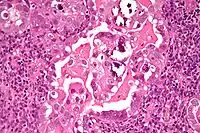

![]() صورة مجهرية ل"سرطانة مصلية حليمية رحمية" بصبغة H&E. صورة مجهرية ل"سرطانة مصلية حليمية رحمية" بصبغة H&E. | |

وبانسبة لعلم أمراض الأنسجة فإن سرطان المصل الرحمي عادة يتميز ب:

(1) بنيات على شكل حلمة (الحليمات) مع نوى ليفية وعائية (2) اللانمطية النووية (عدم انتظام في الغشاء النووي، الحجم النووي الكبير)، (3) أجسام رملية و (4) أهداب.